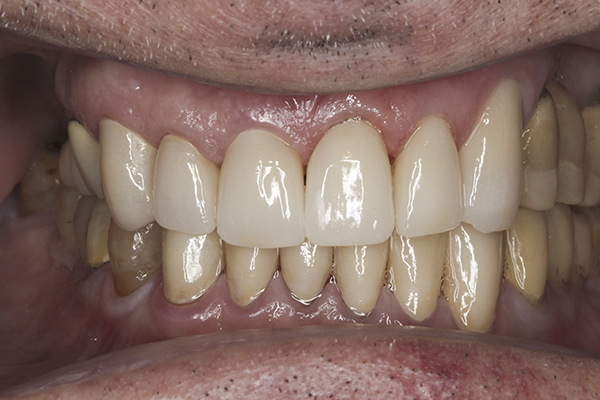

(36.) Postoperative anterior, closed view. Note the position of the upper and lower canines to provide canine guidance.

Figure 36

Based on examination of the mounted models, it was decided to treat the patient in centric relation and an additive equilibration approach was used to idealize the planes of occlusion. On the articulator, the patient’s first point of contact in centric relation was the starting point and an additive equilibration technique was implemented, building the teeth to meet ideally at the patient’s first point of contact. A diagnostic wax-up was completed on the mounted models to determine where the anterior and posterior teeth needed to be in space. A template from the wax-up was used to fabricate the anterior provisional restorations. The anterior teeth were restored with full-coverage restorations, creating ideal stops between the lower incisal edges and upper cingulums. The maxillary incisal edges were placed to provide proper phonetics and an acceptable esthetic outcome, while still working within the envelope of function. All of these parameters are worked out in the provisionals prior to moving forward with definitive restorations. With the anterior provisionals in place, posterior composite tops were bonded to his existing dentition, creating ideal centric stops on the posterior teeth. The anterior and canine guidance was developed, resulting in immediate separation of the posterior teeth during all excursive movements (Figure 17 through Figure 28). Once the author and patient were happy with the function, esthetics, phonetics, and comfort of the provisionals, an impression of the approved provisionals was taken and sent to the laboratory to use as a guide in the fabrication of the final anterior crowns. With the final restorations delivered, the patient was extremely happy with his new smile. Most importantly, proper anterior and canine guidance in harmony with his envelope of function was achieved, which resulted in comfortable function and immediate separation of the posterior teeth during protrusive and lateral excursions (Figure 29 through Figure 42).